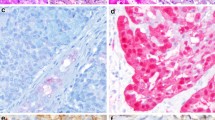

While prognostically useful, it is unclear whether grading of adenoid cystic carcinoma is useful in patient management. Regardless of grade, all adenoid cystic carcinomas are treated with surgery plus irradiation because locally they are aggressive and ‘high risk’. With regard to the neck, most decisions on the neck dissection will not depend on grade, though there is some evidence to suggest that solid/grade 3 adenoid cystic carcinomas have a higher likelihood of lymph node metastasis [3]. With regards to this point, the rare phenomenon of dedifferentiation or high grade transformation may have relevance. Adenoid cystic carcinoma with high grade transformation refers to the presence of a pleomorphic mitotically active high grade carcinoma component arising in an otherwise conventional adenoid cystic carcinoma of any pattern/grade (Fig. 3a) [15]. The transformed component is typically of a purely ductal phenotype with a solid or cribriform appearance. Unlike conventional adenoid cystic carcinoma, which is characterized by small, hyperchromatic, monomorphic nuclei, and scant cytoplasm, transformed components show prominent nuclear size and chromatin variability. Common features include fibrocellular desmoplasia, abundant mitoses, necrosis, and microcalcifications. Unique patterns in high grade transformation include micropapillary and squamoid growth. However, there is still morphologic overlap between solid conventional adenoid cystic carcinoma and high grade transformation and the transition from conventional adenoid cystic to high grade transformation is often gradual. Table 4 delineates key distinguishing features between solid conventional adenoid cystic carcinoma and adenoid cystic carcinoma with high grade transformation. Basically, the aggressive nuclear, stromal, architectural and immunohistochemical features common to both variants are more exaggerated in high grade transformation, while solid conventional adenoid cystic carcinoma shows only slight deviation from tubular or cribriform conventional adenoid cystic carcinoma.

These tumors have an exceptionally poor prognosis with a median survival ranging from 12 to 36 months, and may thus be even more aggressive that solid or ‘grade 3’ adenoid cystic carcinoma. Unlike conventional adenoid cystic carcinoma, this tumor has a lymph node metastatic rate of over 50% (Fig. 3b). Thus if a transformed component is found in an adenoid cystic carcinoma, a neck dissection is likely warranted.